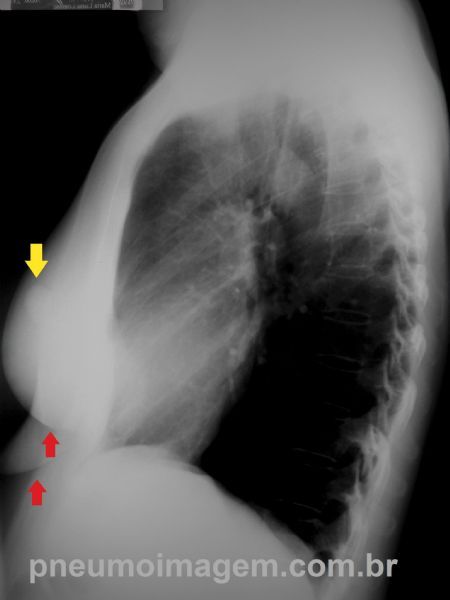

Nódulo isolado projetado sobre o pulmão esquerdo (seta amarela). As setas vermelhas apontam a grande assimetria entre as mamas.

Chaves: Isolated nodule in the left lung (yellow arrow). Large asymmetry between the breasts (red arrows).

Pela radiografia em perfil pode-se observar que o nódulo encontra-se projetado sobre as partes moles.

O exame clínico constatou ser o mamilo esquerdo. As setas vermelhas apontam o contorno das mamas e a grande assimetria entre elas.

Chaves: By the lateral film the nodule is located on the soft parts. Clinical examination found to be the left nipple. The red arrows indicate the contour of the breasts and large asymmetry between them.